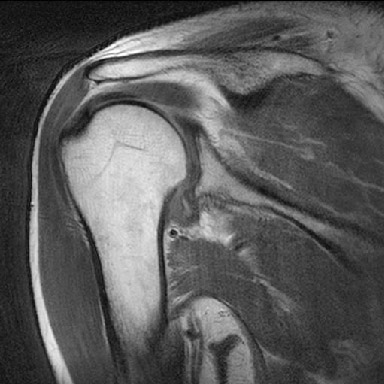

Rt.. Shoulder adhesive capsulitis

견관절낭염 환자의 방사선 영상